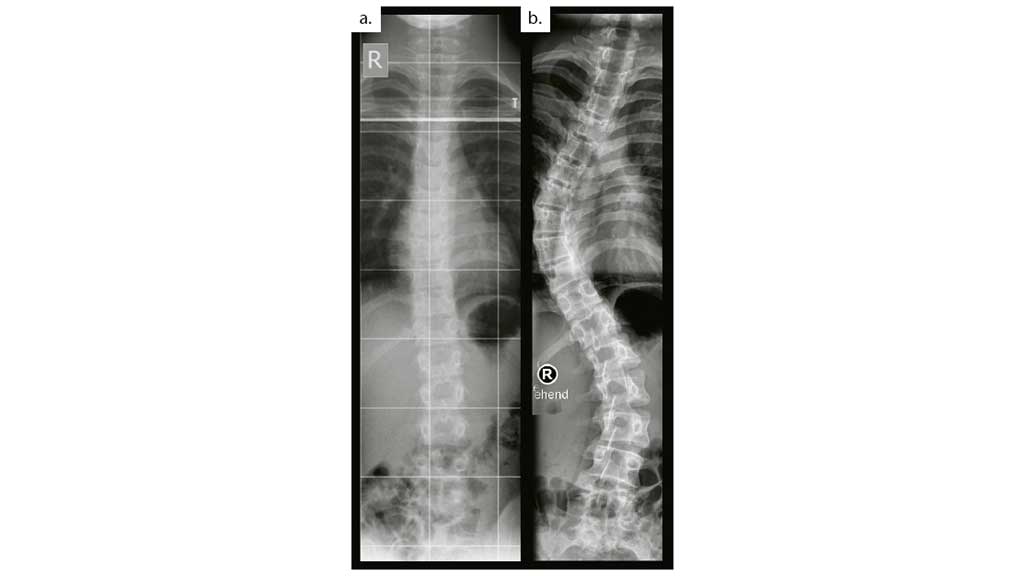

Fortgeschrittene idiopathische Skoliosen entstehen oft aus zunächst nahezu geraden Wirbelsäulen. Zwischen den beiden Röntgenaufnahmen (Abb. 1a und b) liegen nur fünf Jahre. Es ist die Kunst des Behandlungsteams aus Arzt, Physiotherapeut und Orthopädietechniker, im richtigen Augenblick die richtigen Therapien anzuwenden, um Progredienzen schonend und dennoch wirksam einzudämmen. Dabei ist das Team auf die Zuarbeit von Kinderärzten und die Mitarbeit der Patienten angewiesen. Es wird (trotz aller Bemühungen) immer Fälle geben, die mit einzelnen Therapieformen nicht beherrschbar sind, aber das ist kein Grund, am geeigneten Punkt auf mögliche Behandlungsschritte zu verzichten bzw. einzelne Therapieschritte auszulassen oder zu überspringen.